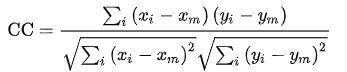

单模图像配准常使用 相关性(Correlation Coefficient, CC)来衡量效果;而多模图像配准常使用 互信息(Mutual Information, MI)衡量。

1. 相关性

相关性本质上是一种相似性度量,它可以了解浮动图像和参考图像的相似程度。如果两个图像完全相同,则相关性等于1;而如果两个图像完全不相关,则相关性值等于0;若相关性值等于-1,表示图像完全反相关,这意味着一个图像是另一个的负面。通过使用相关性作为评价标准,单模态配准可获得满意的结果。

对于同一物体由于图像获取条件的差异或物体自身发生的小的改变而产生的图像序列,采用使图像间相似性最大化的原理实现图像间的配准,即通过优化两幅图像间相似性准则来估计变换参数,,主要是刚体的平移和旋转。相关性主要限于单模图像配准,特别是对一系列图像进行比较,从中发现由疾病引起的微小改变。

它表示为:

x_i , y_i 分别为浮动图像和参考图像第 i 个像素的强度;

x_m , y_m 为 浮动图像和参考图像的平均强度。